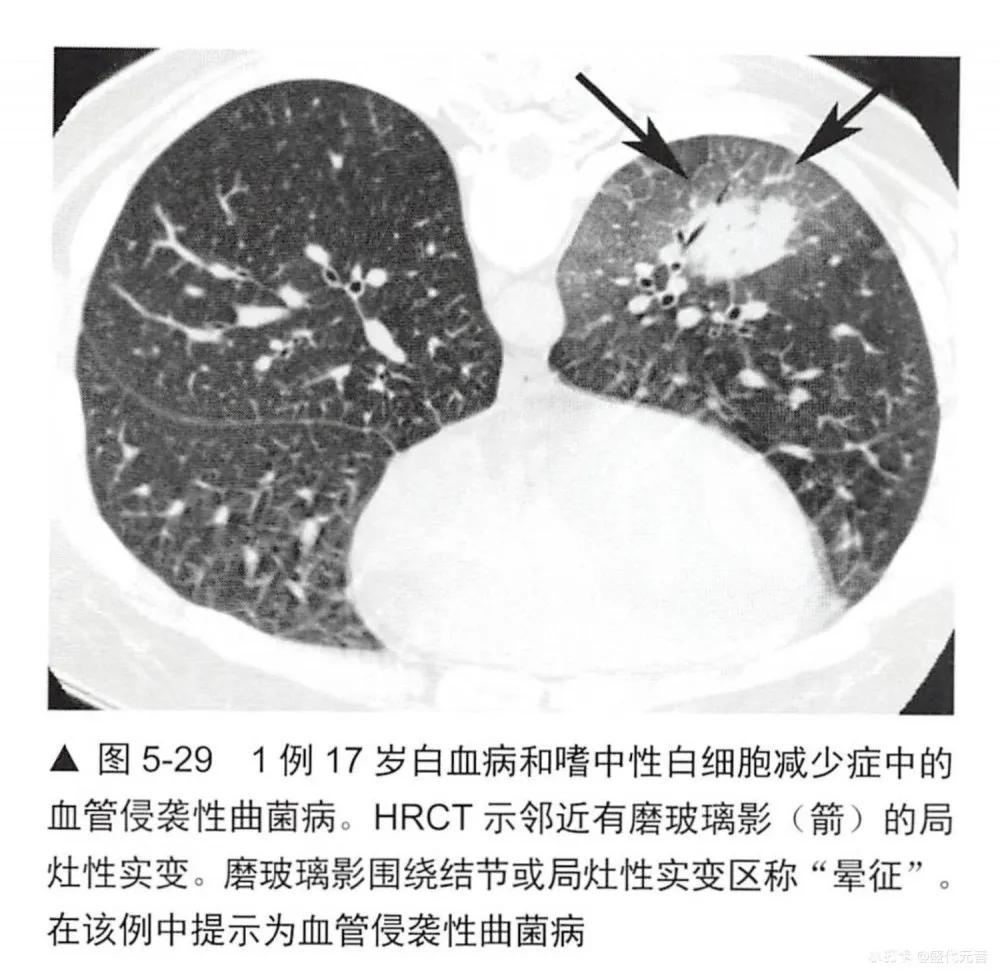

实变是指肺衰减增加并掩蔽了肺血管(图5-1,图5-24〜图5-28)可有空气支气管征(图5-28)。如胸片上已可见明确的实变证据时,HRCT对病例的诊断几乎无帮助。无论如何,HCRT可在胸片有诊断性之前检出实变。实变可伴有局灶性磨玻璃影和小叶中心性结节(图5-28,图5-29)。

实变的鉴别诊断与磨玻璃影(表5-1)有相当大的重叠,事实上,许多表5-1列出的疾病都显示为这两种表现的混合(表5-5)。实变的鉴别诊断包括不同原因的肺炎:最典型的是细菌性(图5-28),但也包括分枝杆菌、真菌性肺炎(图5-29)、支原体、耶氏孢子菌和病毒性肺炎; 0P (图5-24和图5-25);嗜酸性肺炎(图5-26,图5-27),如NSIP和DIP的间质性肺炎;HP (图5-30);放射性肺炎、浸润性黏液腺癌(图5-16和图5-31); LIP;淋巴瘤(图5-32)和淋巴增生性疾病;肺泡蛋白沉着症;结节病;药物反应,肺水肿和肺出血;AIP, DAD和ARDS。与吸入动、植物油脂或矿物油有关的外源性类脂性肺炎,可导致磨玻璃影或实变,此时因含有脂肪是低衰减的(图5-33)。